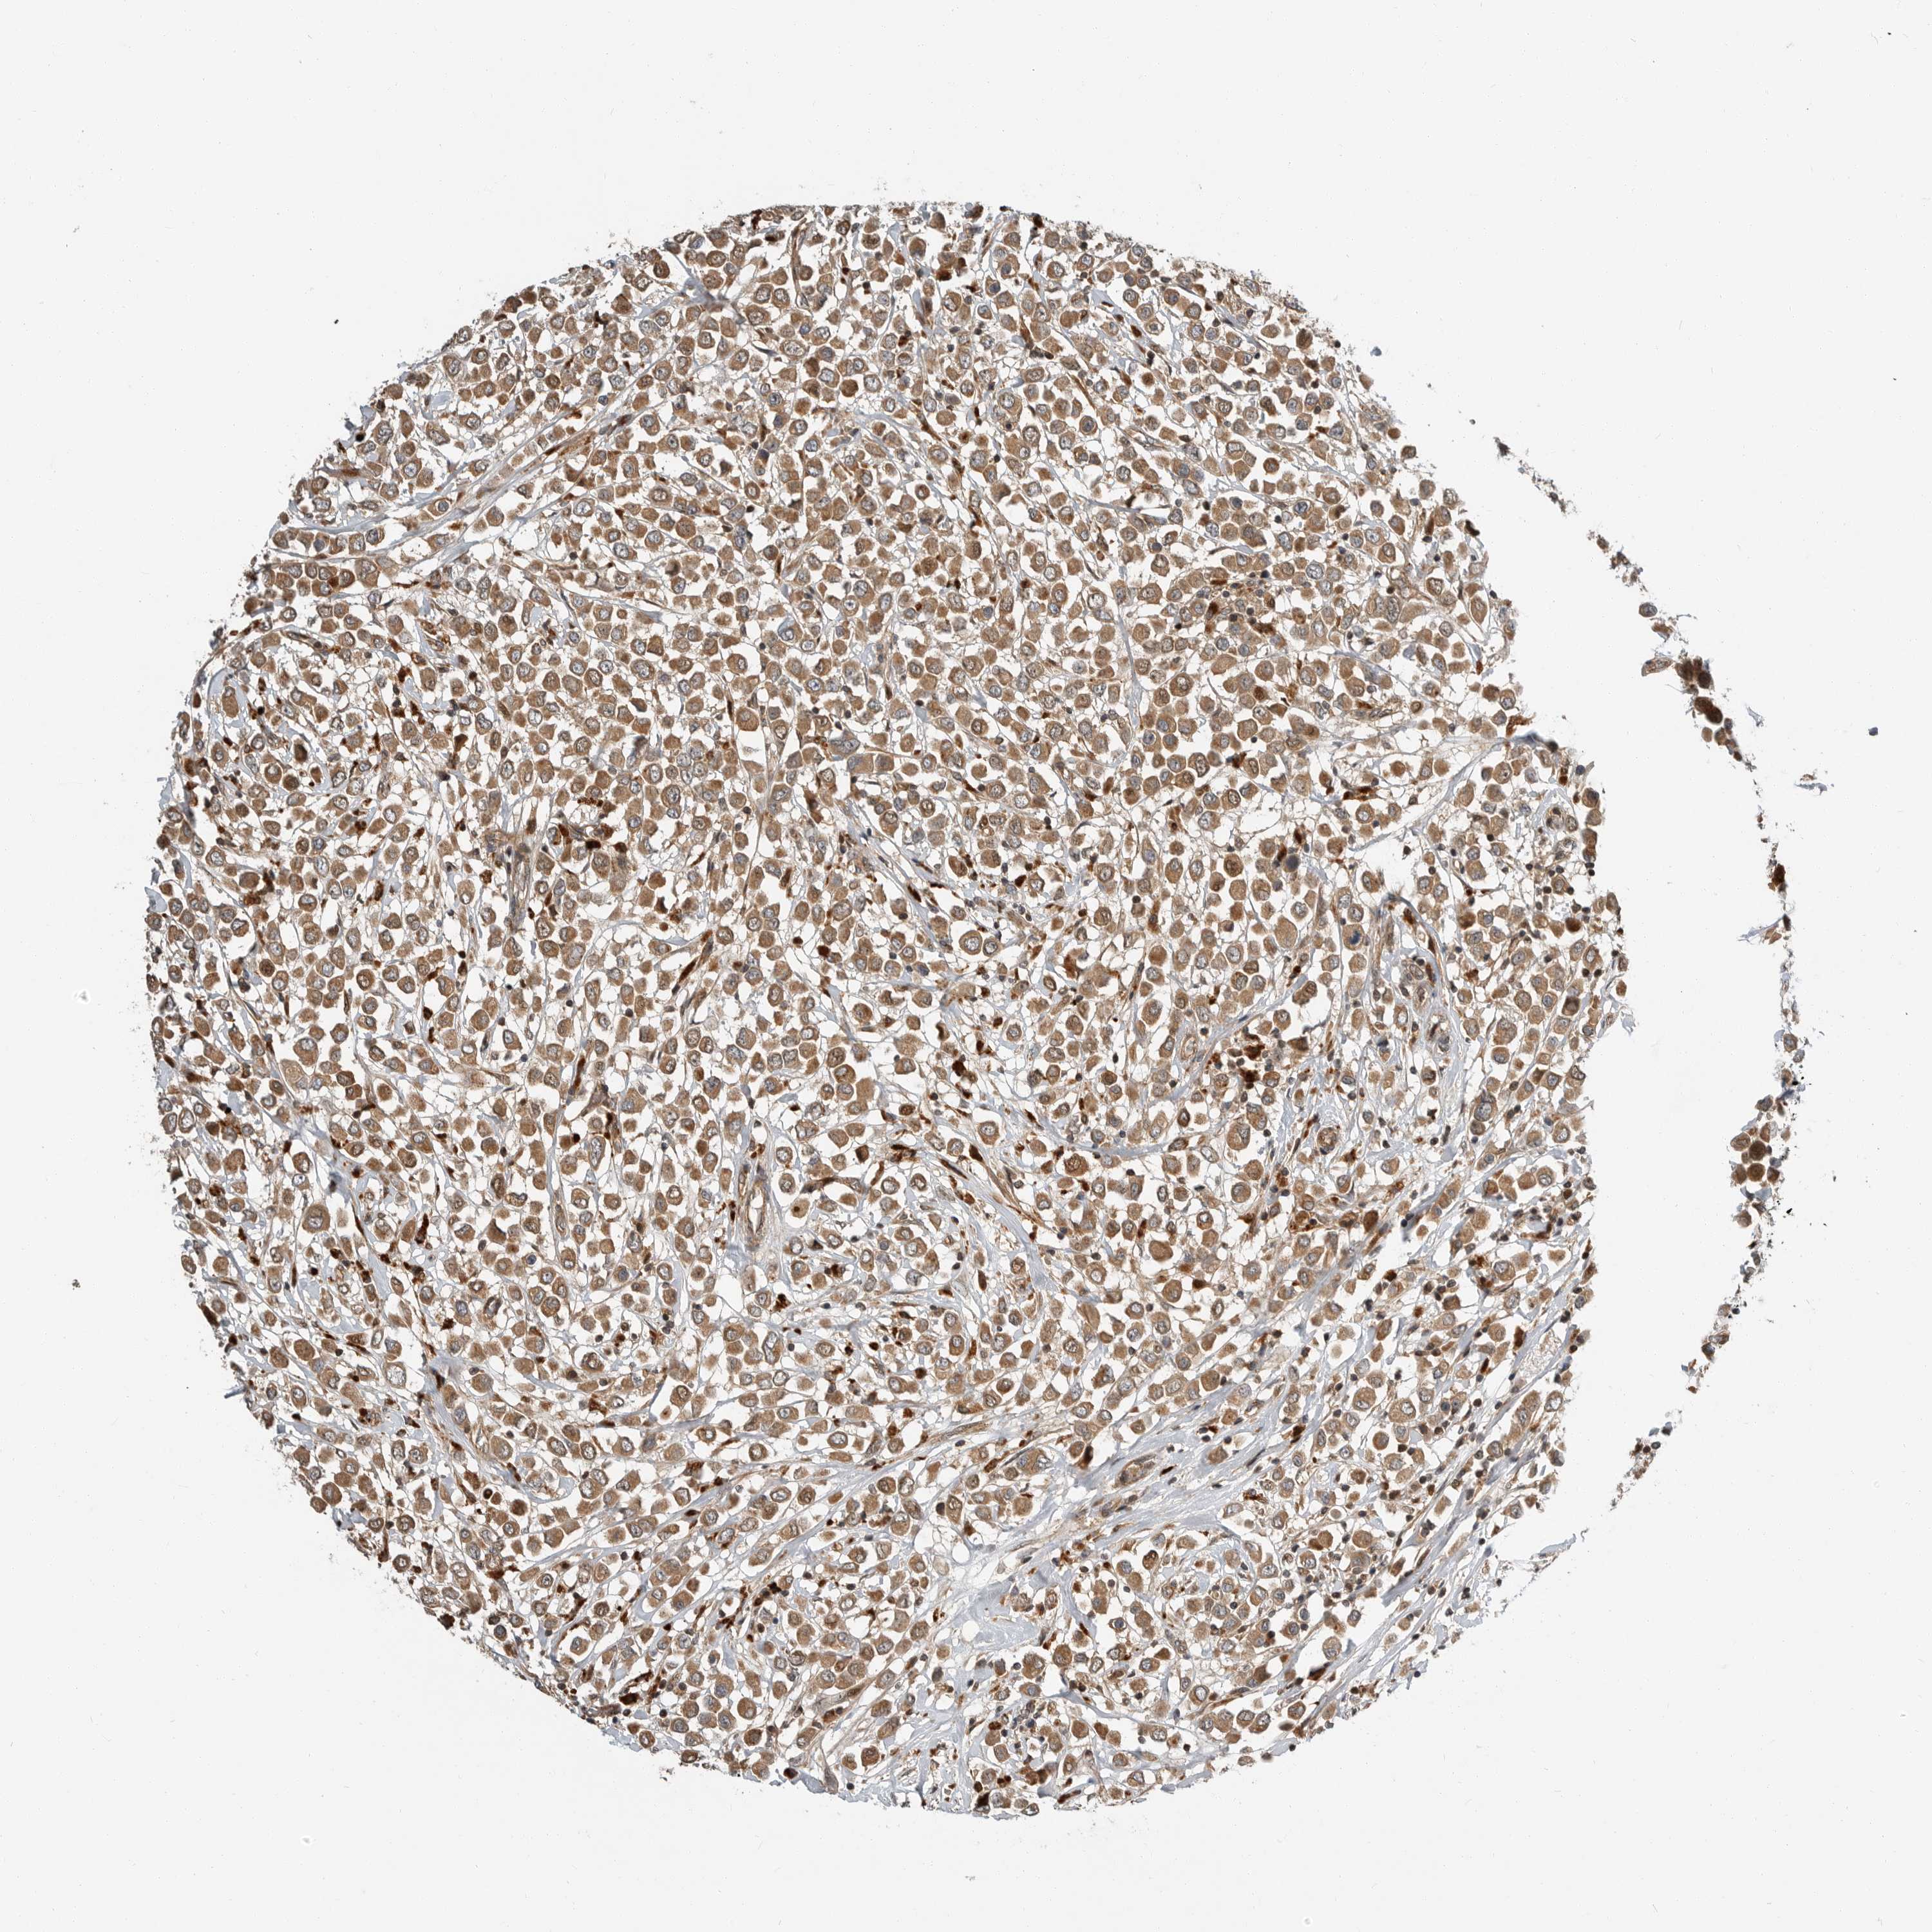

CANCER BREAST CANCER Show tissue menu

Breast cancer

Human cancer